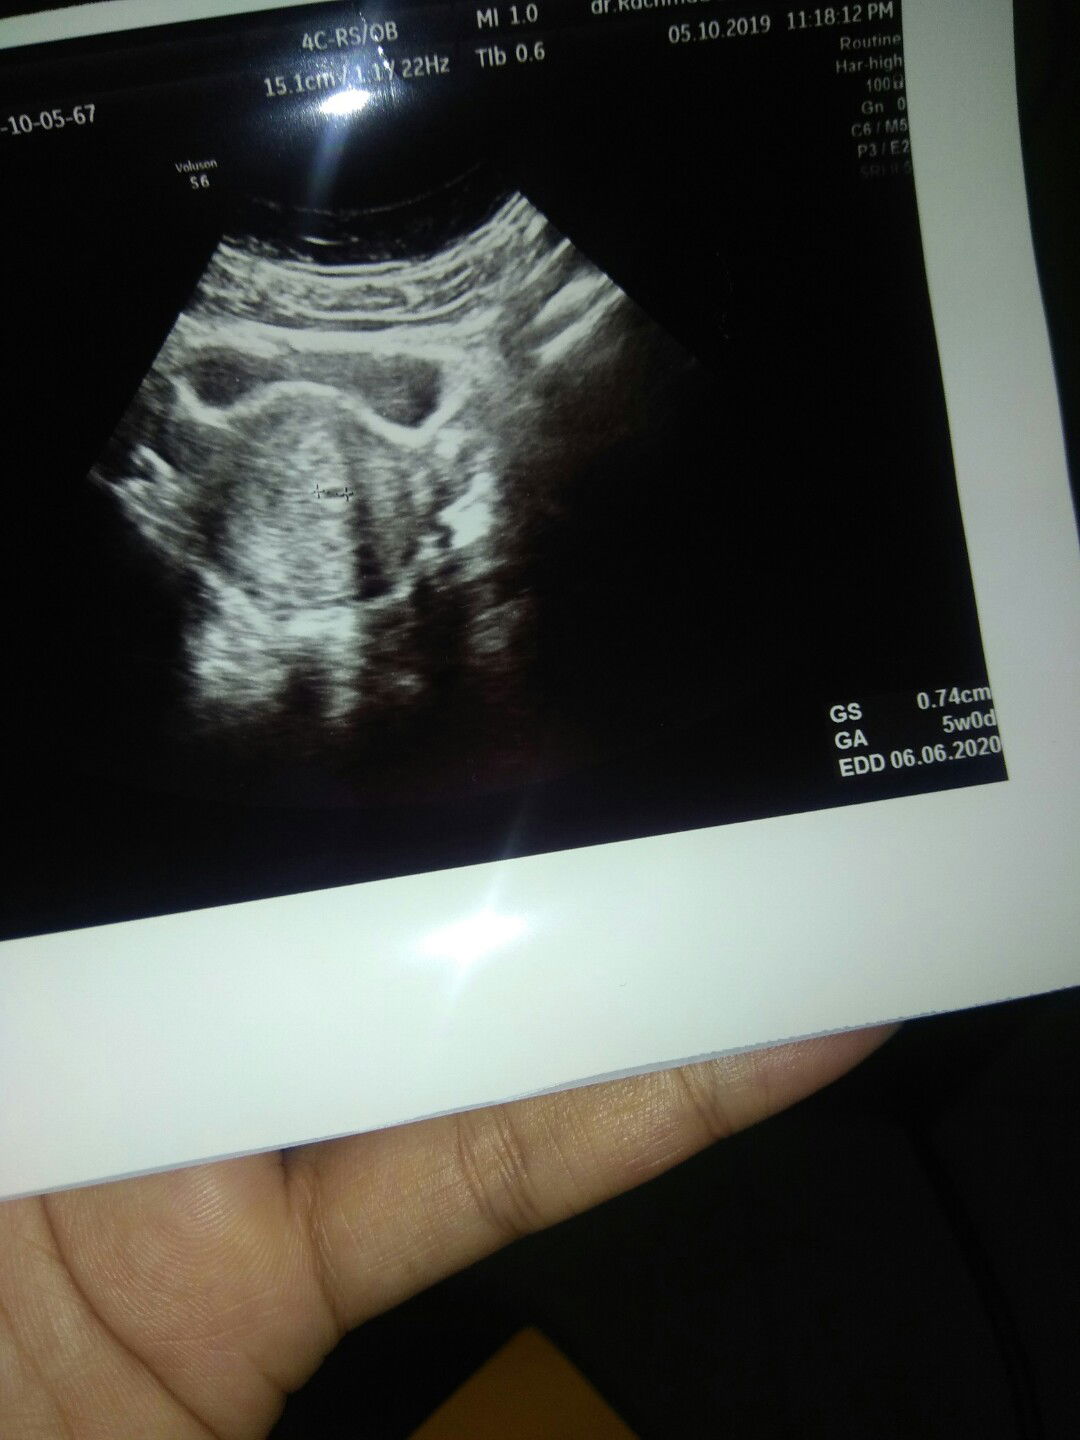

USG 5 Minggu

Hai mom Mau sharing aja nih,ini hasil USG kandungan 5w Umur kandungan menurut HPHT 6w2d tp menurut hasil USG 5w0d USG masih menunjukkan kantung kehamilan saja,menurut dokter itu hal wajar. Nanti 2-3 mnggu balik lg untuk USG Hal-hal yg disarankan dokter agar janin tumbuh kembangnya baik (karena sy ada riwayat keguguran 2x) yaitu: - Minum susu sehari sekali - Minum vitamin (dokter meresepkan folamil genio) - Kurangi makanan yg dibakar,mentah,terlalu berminyak,terlalu bersantan kental,terlalu pedas,terlalu asam dan pahit - Perbanyak minum air putih untuk menghindari ISK - Konsumsi telur dan es krim